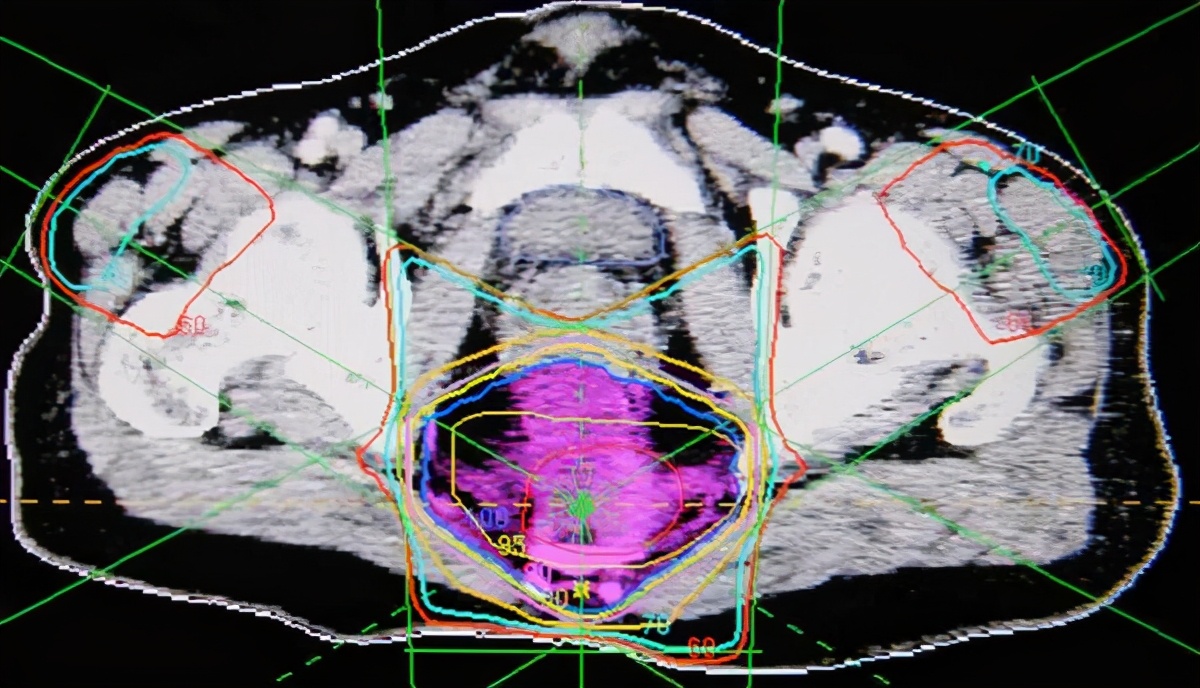

对于直肠癌局部盆腔复发,一般不首先手术切除。这种情况下,单纯再次手术很困难,一是术后粘连严重,再次手术出血风险增加,再者术中难以明确转移的病灶,尤其是病灶不大的情况下。因此,对于,直肠癌局部复发后的治疗,建议化疗联合局部放疗(前提是术前没有根治性放疗),同时完善分子检测,选择合适的靶向药物。